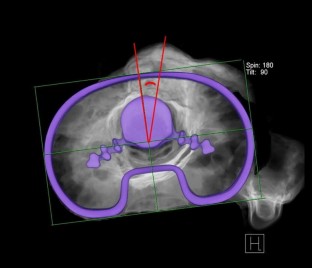

Optimal rotational positioning of tibial component in total knee arthroplasty: determined by linker surgical technique using a high definition CT

The rotational alignment of femoral and tibial components is an important determinant of the success of Total Knee Arthroplasty (TKA). The optimal rotational position of the tibial component is still unclear. The purpose of this study was (1) to determine the pre-operative S-TEA (surgical-transepicondylar axis) derived tibialanteroposterior (AP) axis angle and postoperative tibial component axis angle using a “Bird’s eye” high-definition CT image in TKA performed by Linker surgical technique; (2) to determine the femorotibial mismatch angle; and (3) to determine the optimal tibial component rotation in a well-aligned femoral and tibial components.

The mean angle of the pre-operative tibial AP axis was 17.8° ± 4.0°, ranging from 4.3° to 25.4°. The mean angle of the post-operative tibial component axis was 16.2° ± 4.9°, ranging from 3.8° to 25.2°. The mean postoperative tibial component axis line was at 14.2% ± 11.9%.

Because of the variability of pre-operative S-TEA derived tibial AP axis angle, the tibial component axis angle was also variable among the knees, but the two angles bore a strong correlation to each other. Based on our results, the optimal axis of the tibial component passes about halfway through the medial edge and medial one-third of the tibial tuberosity.

• Preoperative S-TEA derived tibial AP axis angle

• “Bird’s eye” high-definition CT image

• Tibial component rotation

• Mismatch angle